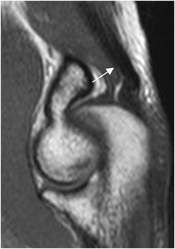

La inserción del tendón del tríceps en el olécranon, se observa mejor en secuencias sagitales. (3). Muestra estriaciones a nivel de su inserción, por interposición de grasa entre los fascículos. (8). (Fig 12 y 13). Puede encontrarse laxitud del tendón en extensión completa del codo, que no debe confundirse con ruptura y se confirma valorando las imágenes axiales. (8). (Fig 14).

Fig 13. Tendón del tríceps normal en RM.

A: RM axial en T1 y B: RM coronal en T1. Estriaciones grasas a nivel de su inserción.